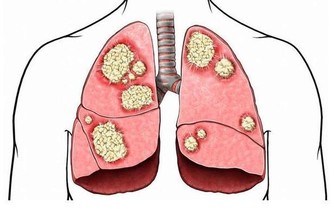

嚴重的甚至會導致骨關節壞死,這種屬於病理性關節響,一般伴隨著疼痛、活動受限,或者關節突然卡住。

如何保護膝關節

現在已經進入冬季了,我們平時一定要做好保暖措施,尤其是膝蓋,可以戴上護膝,千萬不要進風受涼。

如果是膝蓋已經產生損傷的人的話,工作一天回到家,如果膝蓋太難受的話,可以把腿抬高,這樣是可以起到消腫的作用。

久站不動的,要刻意動一動。肌肉疲勞時一定要休息,肌肉虛弱時,關節受到的衝擊傷害成倍增加。